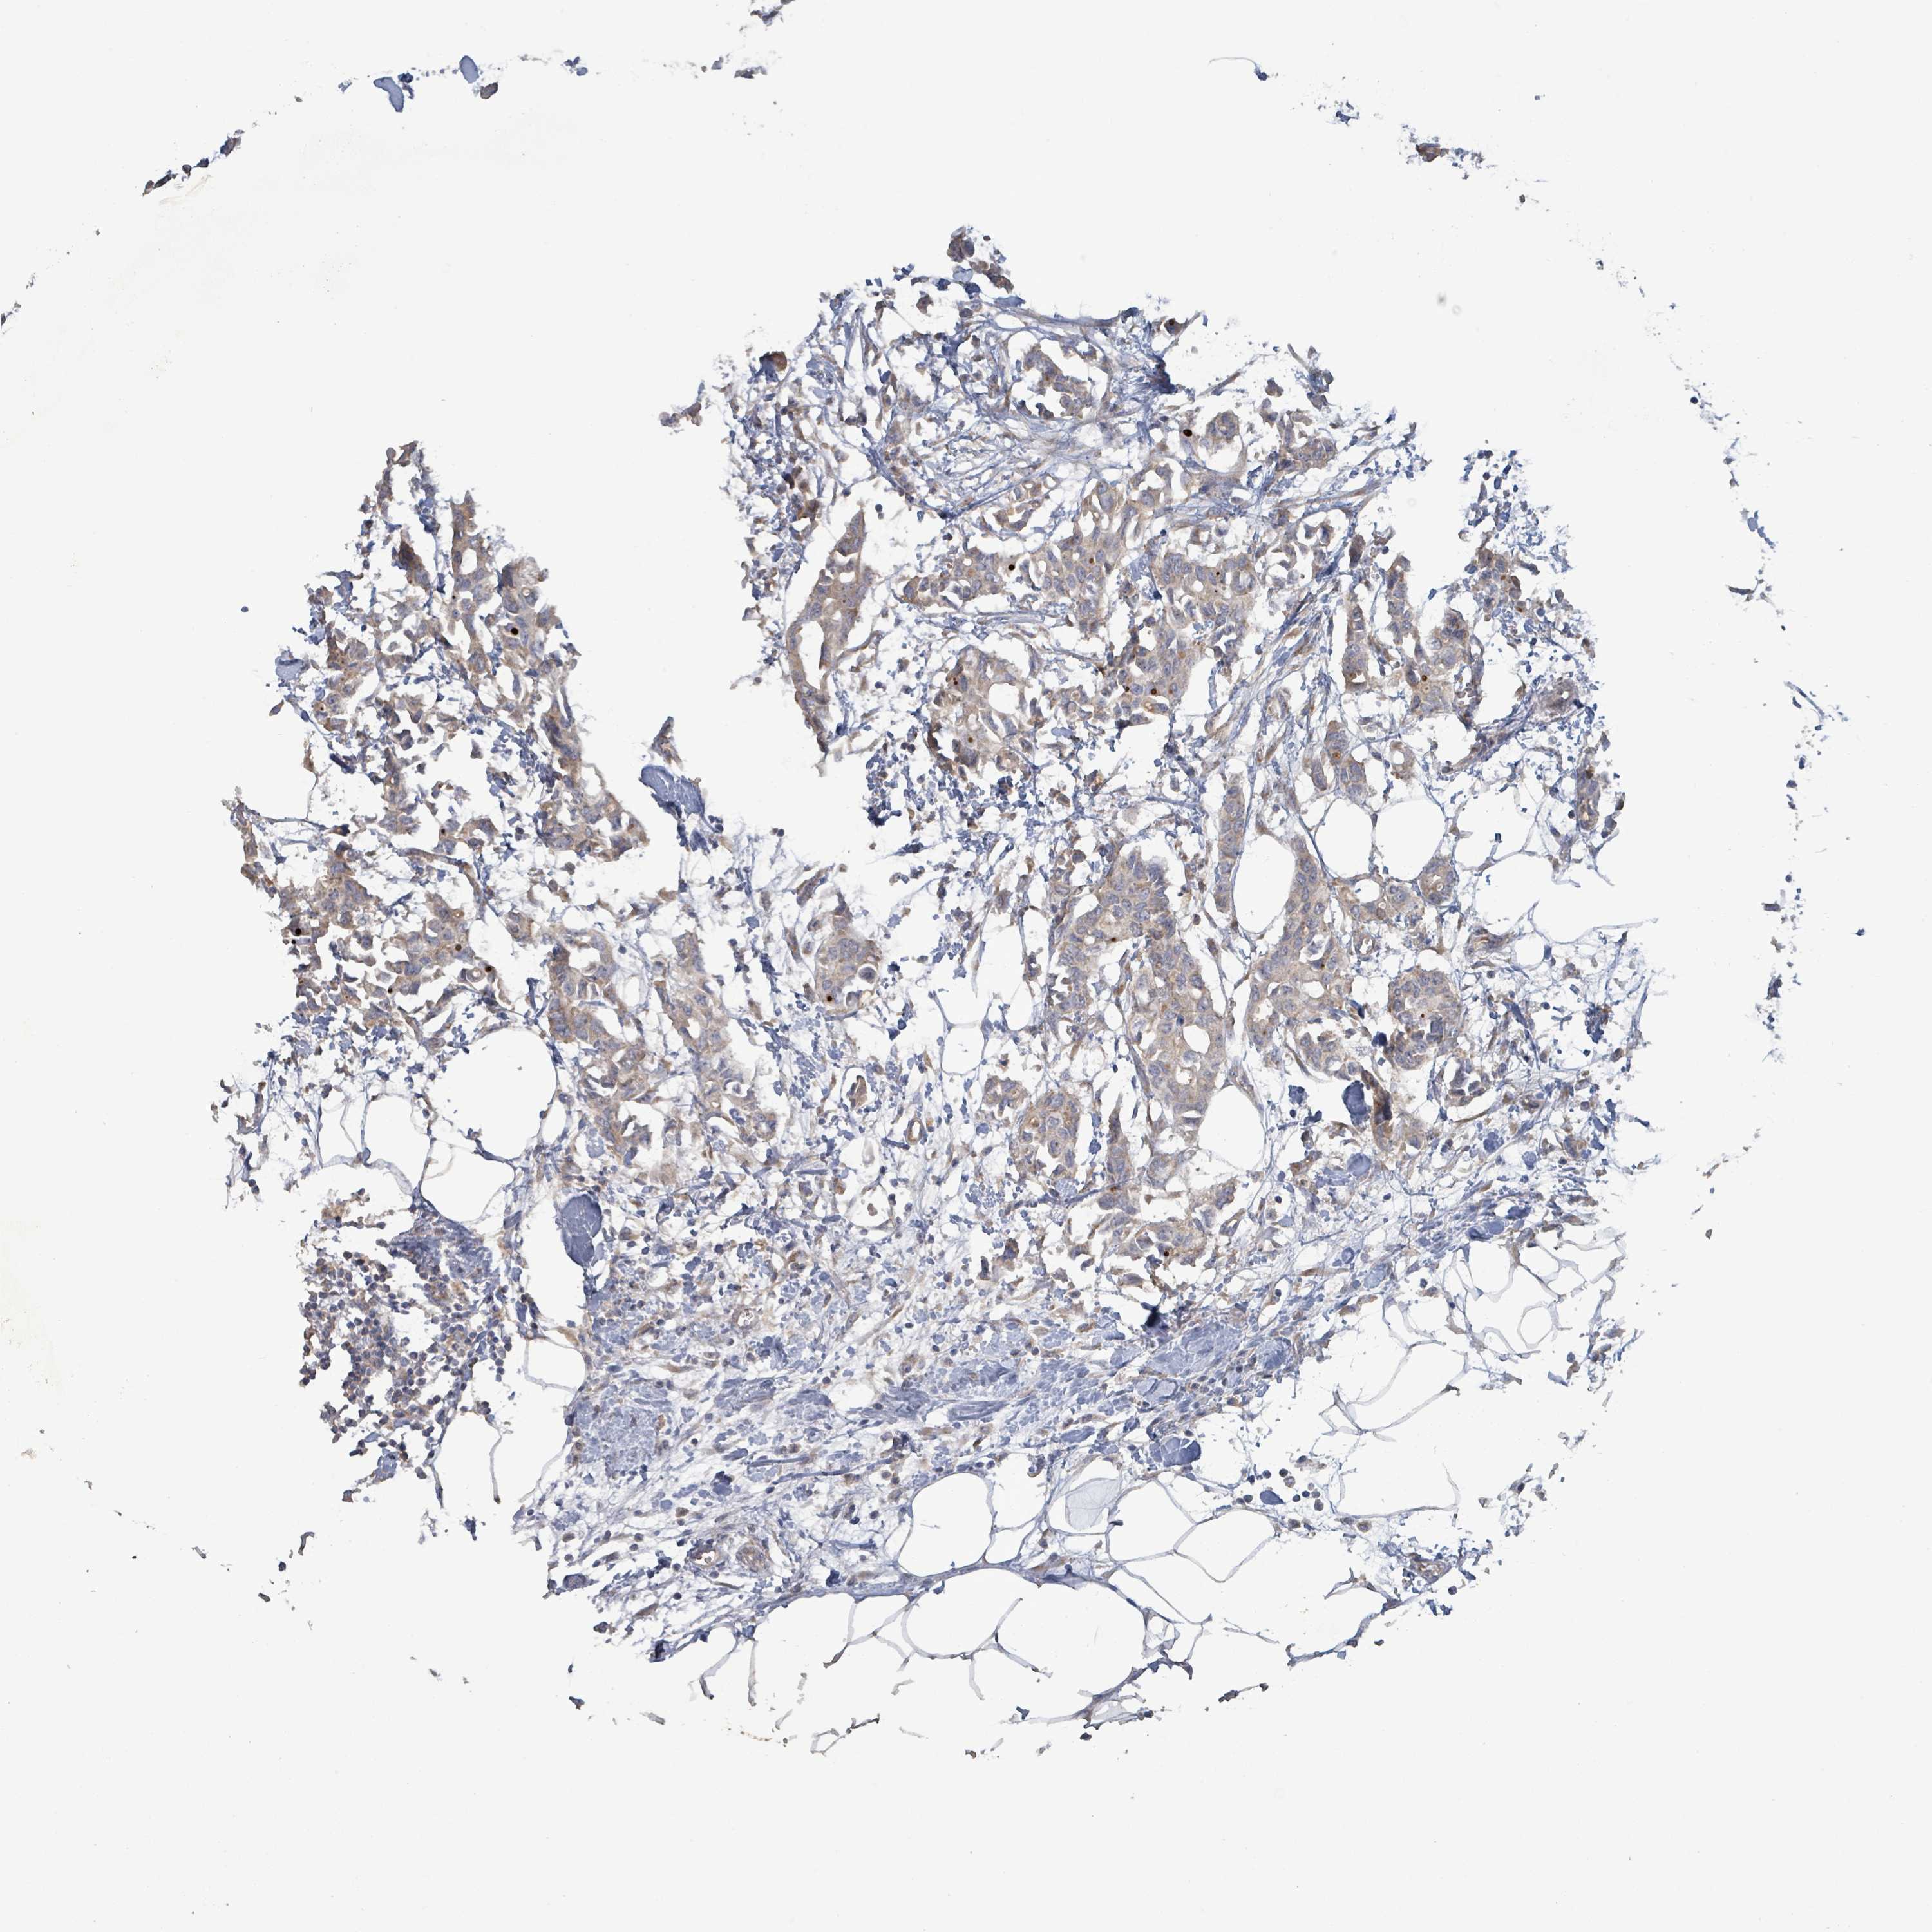

CANCER BREAST CANCER Show tissue menu

BRCA TCGA BRCA VALIDATION PROTEIN EXPRESSION

Breast cancer

Human cancer